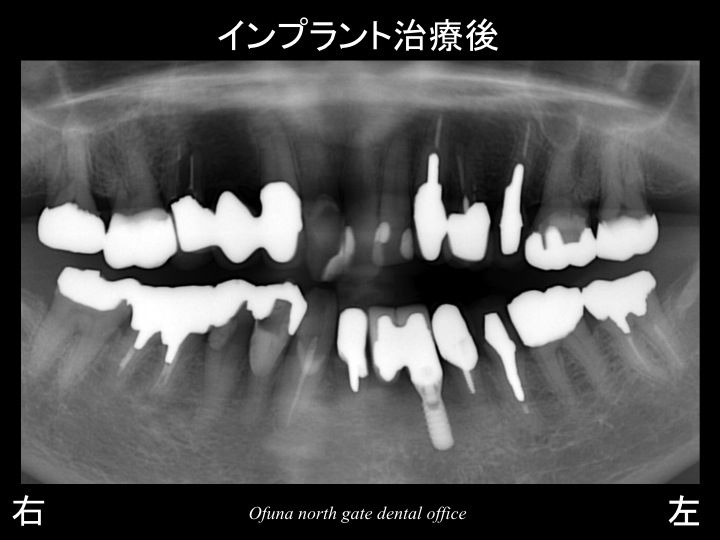

以下のレントゲンは治療後です。

2欠損に対して、1本のインプラントのみを埋入し、2歯分を作製するのです。

下顎の前歯部は、噛む力の負担が加わりにくい部位ですので、

1本のインプラントで2歯分を支えることは可能です。

使用したインプラントは、ストローマンインプラント(ITIインプラント) です。